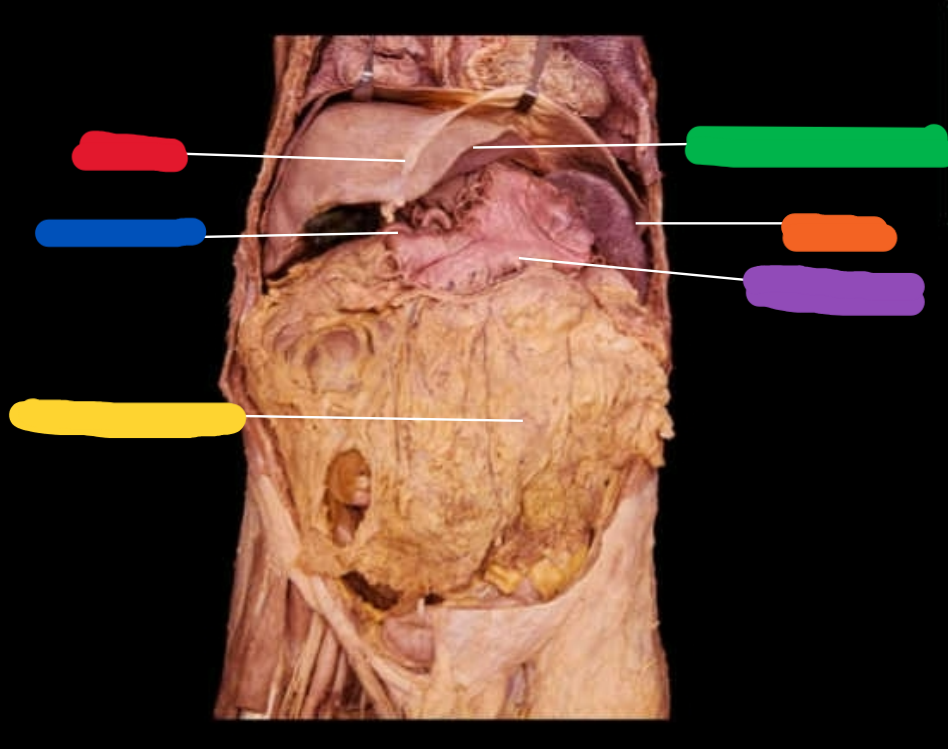

Name the following features highlighted

-Greater omentum

-Small intestine

-Epiploic appendages

-large intestine

-cecum